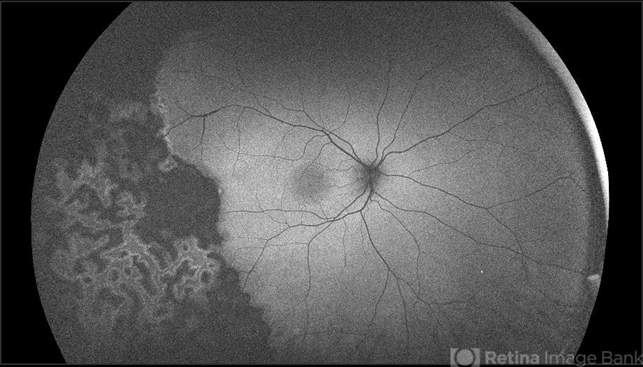

- familial exudative vitreoretinopathy (FEVR), autofluorescence imaging, Optos, ultra-wide field imaging, laser scarring

- Ultra-wide-field autofluorescence image of an 10-year-old male with familial exudative vitreoretinopathy s/p laser.